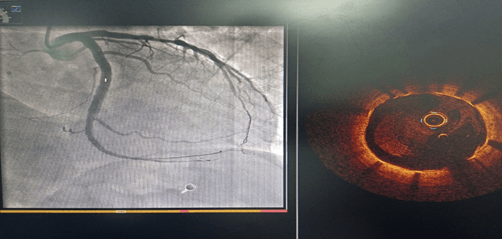

术前CAG示:左主干闭塞 IABP支持下开通闭塞血管